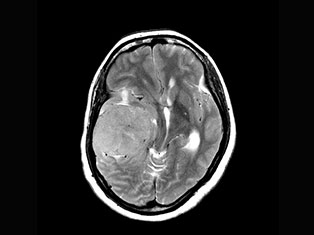

Brain Tumors

A brain tumor is a mass or growth of abnormal cells in your brain. Many different types of brain tumors exist. Some brain tumors are noncancerous (benign), and some brain tumors are cancerous (malignant).